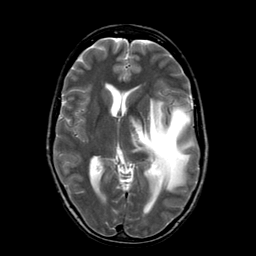

Metastatic bronchogenic carcinoma, overlay -- Slice #11

[Home][Help][Clinical] Slice 11